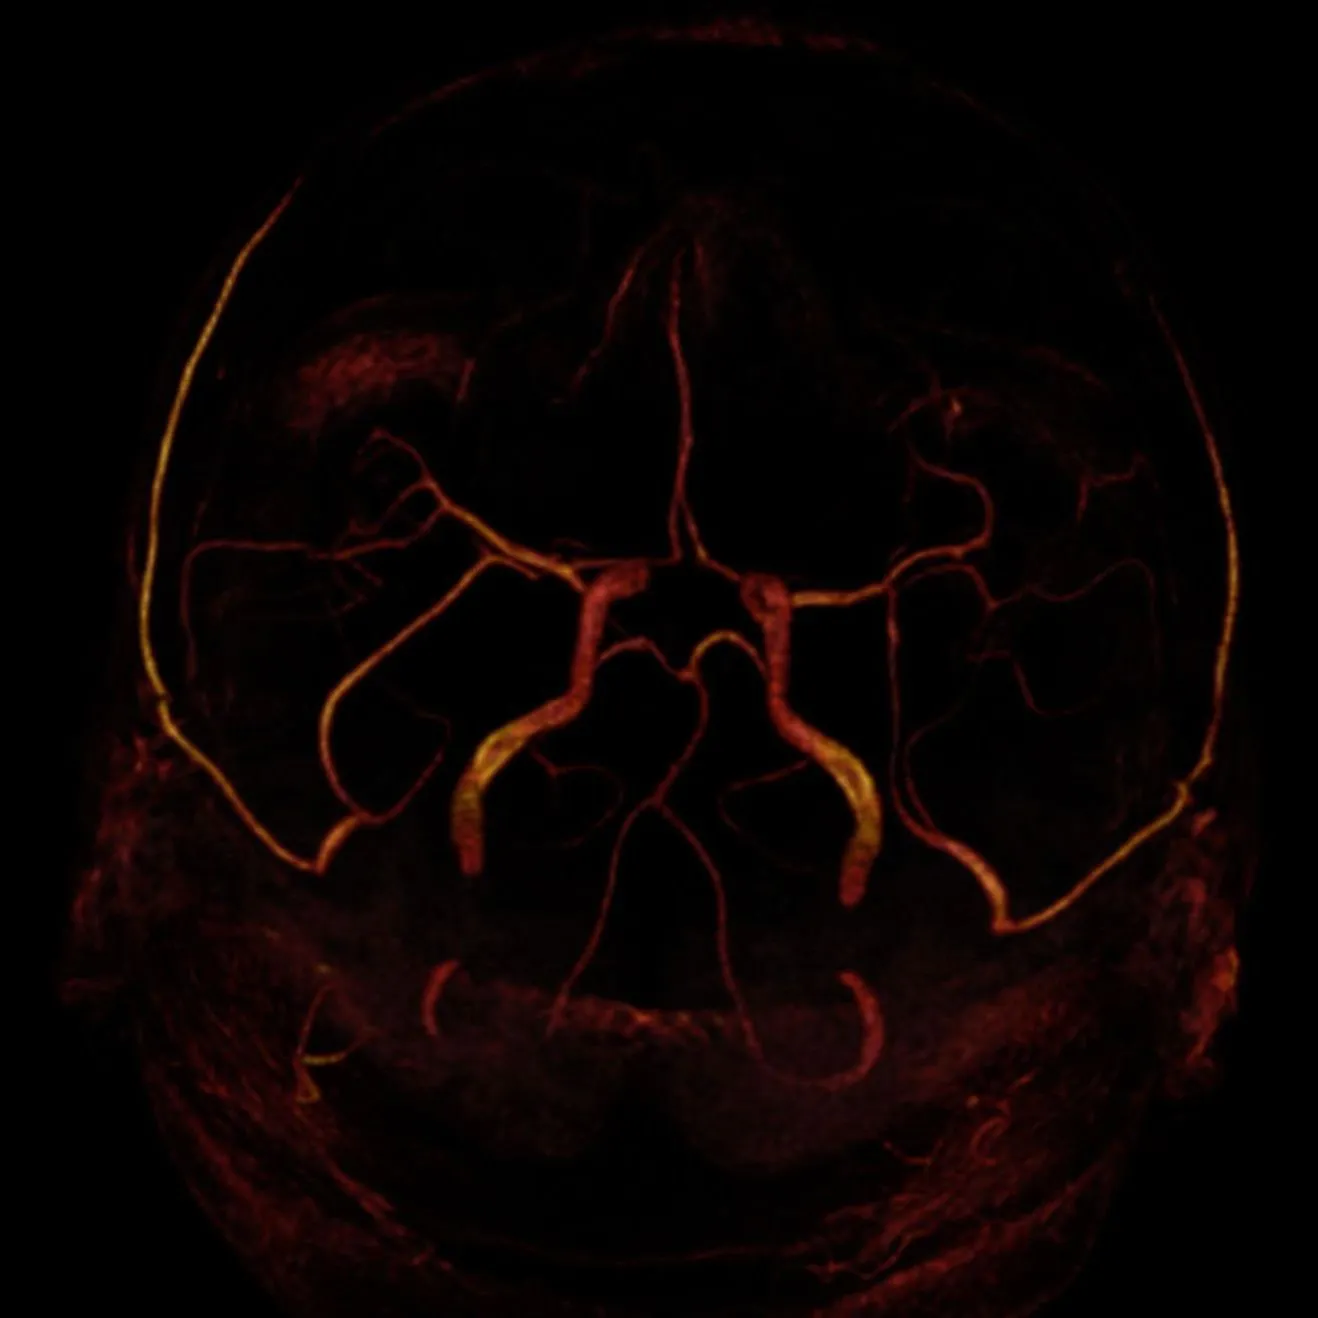

Willis Poligonu 3B Model

Posterior Görünüm

Sağ Oblik

Anterior Görünüm

Tepe

Ölçüm

MRA Ölçüm

MRA MIP

MRA Oblik MIP

MRA VR